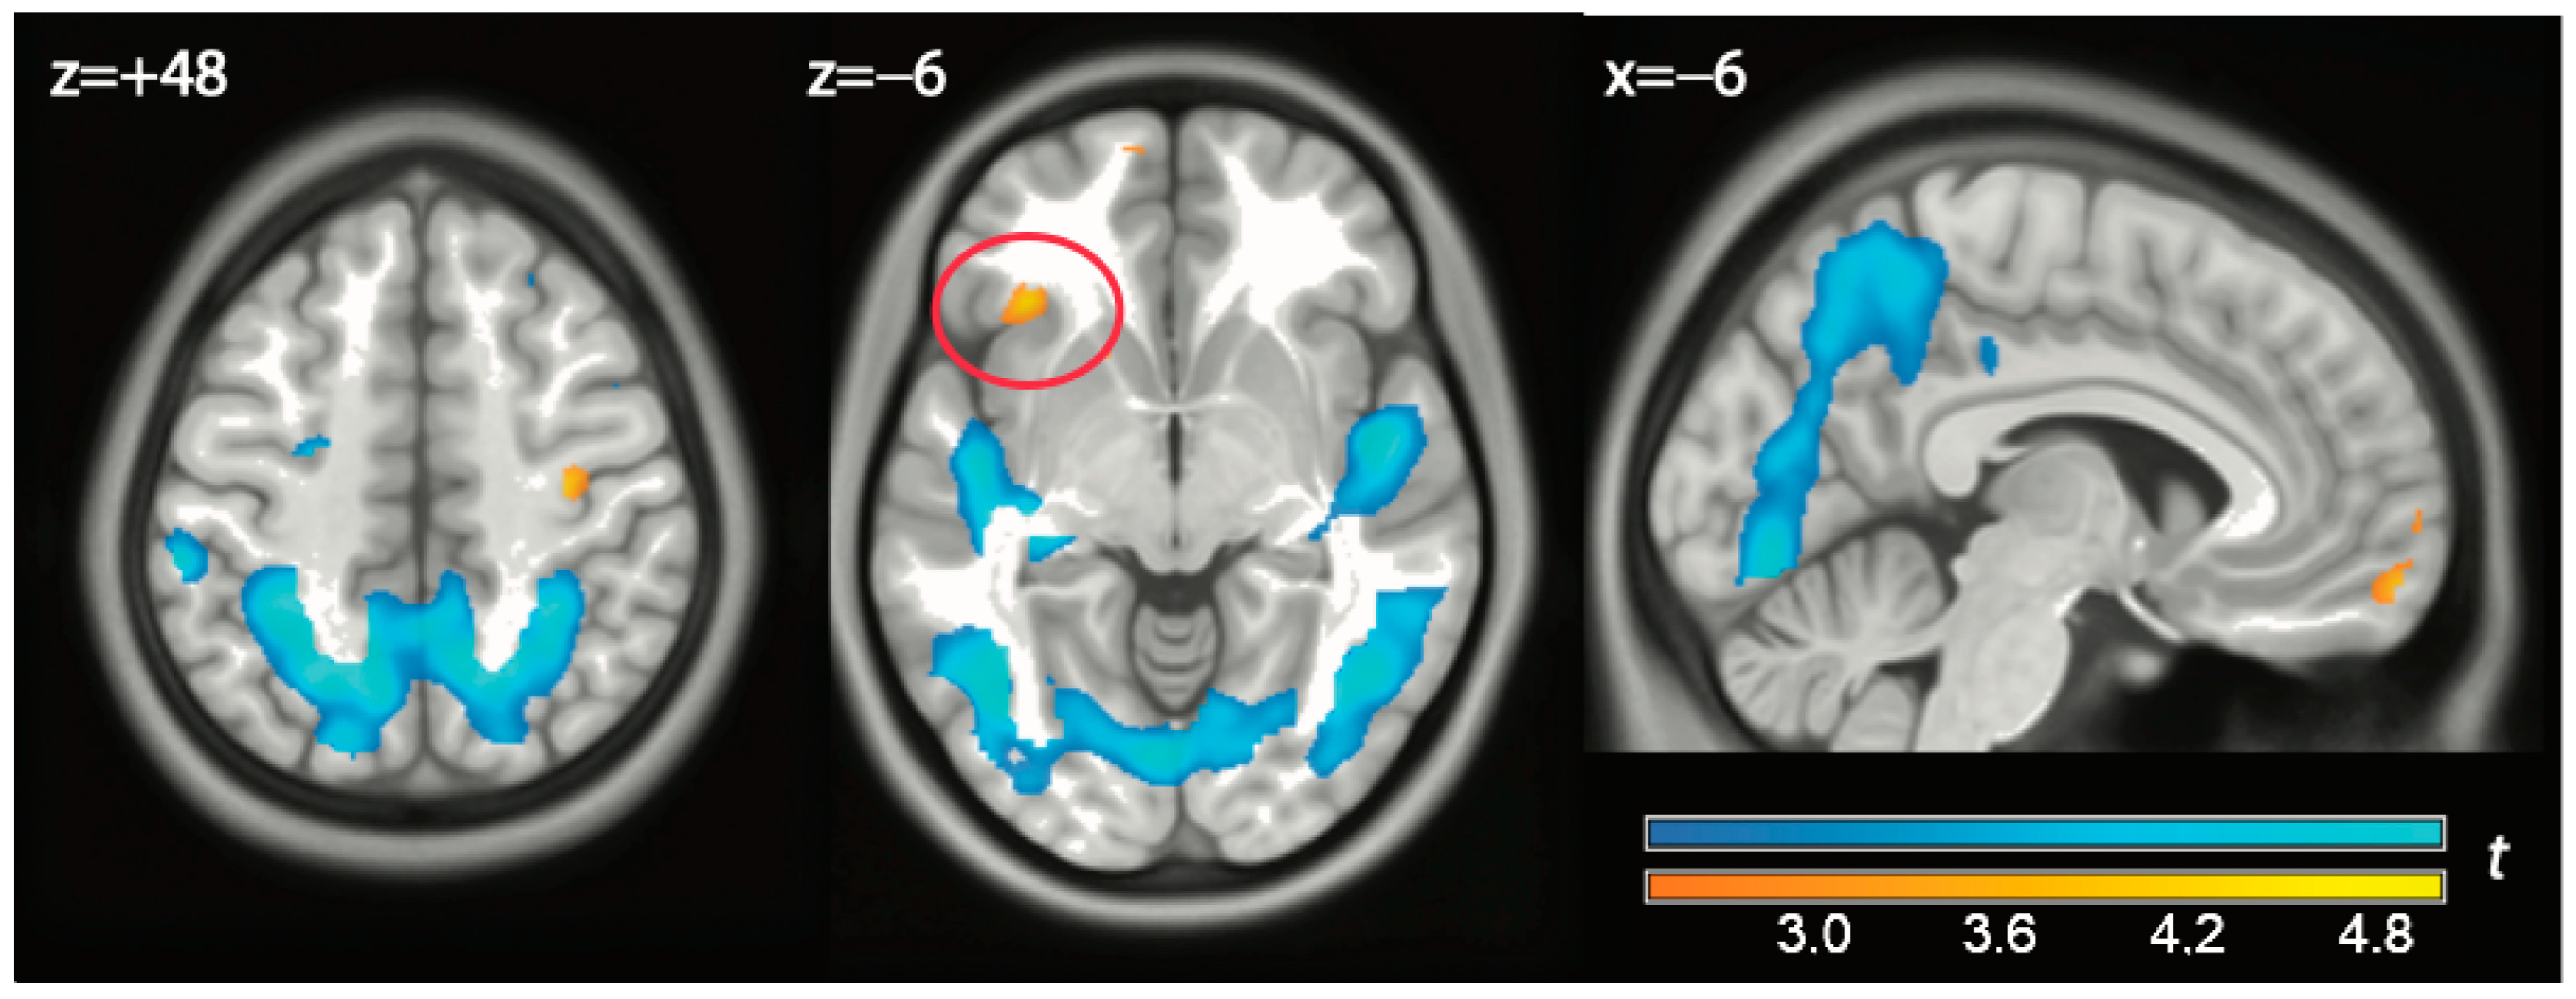

| Watch vs. play | |||||||

| 1 | Right Sup Temporal Gyrus (BA 22) | 58 −12 0 | 7.906 | <0.0001 | <0.001 | 1946 | <0.001 |

| 2 | Left Sup Temporal Gyrus (BA 21) | −42 −28 6 | 6.606 | <0.0001 | 0.004 | 2916 | <0.001 |

| Left Insula | −46 −16 2 | 6.000 | <0.0001 | 0.013 | |||

| Left Insula | −46 −16 18 | 5.810 | <0.0001 | 0.019 | |||

| Left Sup Temporal Gyrus (BA22) | −60 −40 4 | 5.474 | <0.0001 | 0.037 | |||

| Left Sup Temporal Gyrus (BA 22) | −60 −10 −2 | 5.246 | <0.0001 | 0.056 | |||

| Left Sup Temporal Gyrus (BA 22) | −60 −6 10 | 5.237 | <0.0001 | 0.057 | |||

| Left Sup Temporal Gyrus (BA 21) | −64 −28 8 | 4.680 | <0.0001 | 0.167 | |||

| Left Claustrum | −36 −22 −4 | 4.418 | <0.0001 | 0.258 | |||

| Left Sup Temporal Gyrus (BA 42) | −66 −22 12 | 4.386 | <0.0001 | 0.270 | |||

| Left Sup Temporal Gyrus (BA 22) | −60 0 2 | 4.273 | 0.0001 | 0.323 | |||

| Left Inferior Frontal Gyrus (BA 47) | −46 32 4 | 3.890 | 0.0003 | 0.815 | |||

| 0.031 * | 494 | <0.001 * | |||||

| Left Mid Temporal Gyrus (BA 37) | −62 −48 −8 | 3.685 | 0.0006 | 0.653 | |||

| 3 | Left Cingulate Gyrus (BA 31) | −2 −38 40 | 5.640 | <0.0001 | 0.027 | 1253 | 0.001 |

| Left Posterior Cingulate (BA 23) | −10 −48 22 | 5.175 | <0.0001 | 0.067 | |||

| Left Paracentral Lobule (BA 6) | −4 −34 56 | 5.016 | <0.0001 | 0.091 | |||

| Left Posterior Cingulate (BA 30) | −12 −50 20 | 4.829 | <0.0001 | 0.129 | |||

| Left Paracentral Lobule (BA 5) | −8 −36 62 | 4.594 | <0.0001 | 0.193 | |||

| Left Paracentral Lobule (BA 31) | −4 −20 48 | 4.002 | 0.0003 | 0.472 | |||

| Left Posterior Cingulate (BA 17) | −10 −64 12 | 3.801 | 0.0004 | 0.584 | |||

| 4 | Left Subgenual (BA 25) | −8 40 −10 | 4.408 | 0.0001 | 0.464 | 1838 | 0.026 |

| 0.008 * | 635 | <0.001 * | |||||

| Left Orbitofrontal (BA 11) | −4 28 −16 | 3.120 | 0.0023 | 0.999 | |||

| 0.106 * | |||||||

| Play vs. watch | |||||||

| 5 | Right Middle Frontal Gyrus (BA 6) | 32 −6 60 | −6.889 | <0.0001 | 0.001 | 961 | 0.003 |

| Right Sup Frontal Gyrus (BA 6) | 18 12 60 | −6.024 | <0.0001 | 0.011 | |||

| Right Medial Frontal Gyrus (BA 6) | 18 0 54 | −5.363 | <0.0001 | 0.041 | |||

| 6 | Left Middle Frontal Gyrus (BA 6) | −28 −8 48 | −5.562 | <0.0001 | 0.028 | 330 | 0.027 |

| Left Sub-Gyral (BA 6) | −26 −6 58 | −4.749 | <0.0001 | 0.143 | |||

| Left Middle Frontal Gyrus (BA 6) | −36 −4 62 | −4.454 | <0.0001 | 0.243 | |||

| Left Sup Frontal Gyrus (BA 6) | −22 −2 68 | −4.072 | 0.0002 | 0.427 | |||

| 7 | Right Inf Parietal Lobule (BA 40) | 40 −38 44 | −4.755 | <0.0001 | 0.142 | 850 | 0.004 |

| Right Inf Parietal Lobule (BA 40) | 50 −40 40 | −4.454 | <0.0001 | 0.243 | |||

| Exclusion vs. watch | |||||||

| 1 | Left Superior Frontal Gyrus (BA 11) | −16 58 −18 | 3.936 | <0.001 | 0.489 | 18 | 0.430 |

| 2 | Left Inferior Frontal Gyrus (BA 47) | −34 28 −6 | 3.582 | <0.001 | 0.699 | 6 | 0.599 |

| 0.031 * | 50 | 0.053 * | |||||

| 3 | Left Ventromedial Prefrontal (BA 11) | −10 60 −14 | 3.740 | <0.001 | 0.027 * | 67 | 0.050 * |

| Watch vs. exclusion | |||||||

| 4 | Left Superior Temporal Gyrus(BA 42) | −64 −34 18 | −7.602 | <0.001 | 0.001 | 3615 | <0.001 |

| 5 | Right Superior Parietal Lobule (BA5) | 18 −58 62 | −7.306 | <0.001 | 0.001 | 2949 | <0.001 |

| 6 | Right Insula(BA 13) | 40 −20 6 | −5.307 | <0.001 | 0.047 | 1220 | 0.003 |

| 7 | Right Fusiform (BA 19) | 40 −72 −20 | −4.928 | <0.001 | 0.099 | 1249 | 0.003 |

| 8 | Left Superior Frontal (BA 6) | −24 −8 54 | −4.466 | <0.001 | 0.228 | 36 | 0.309 |

| 9 | Left Middle Occipital Gyrus (BA 39) | −42 −76 20 | −4.238 | <0.001 | 0.331 | 44 | 0.275 |